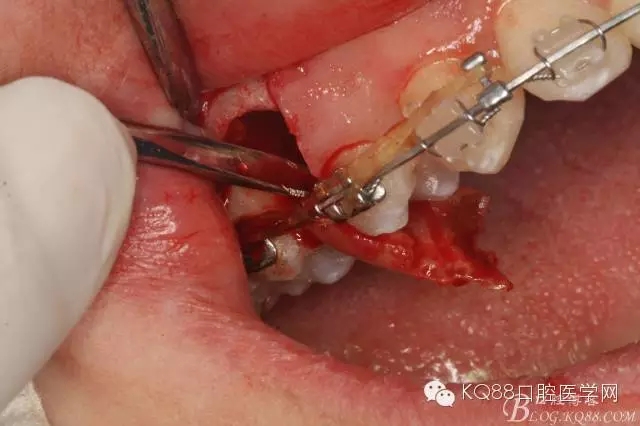

图13. 用小球钻去除约1mm牙槽骨,暴露15牙根面约5mm。

图14.用小球钻纵分15牙根